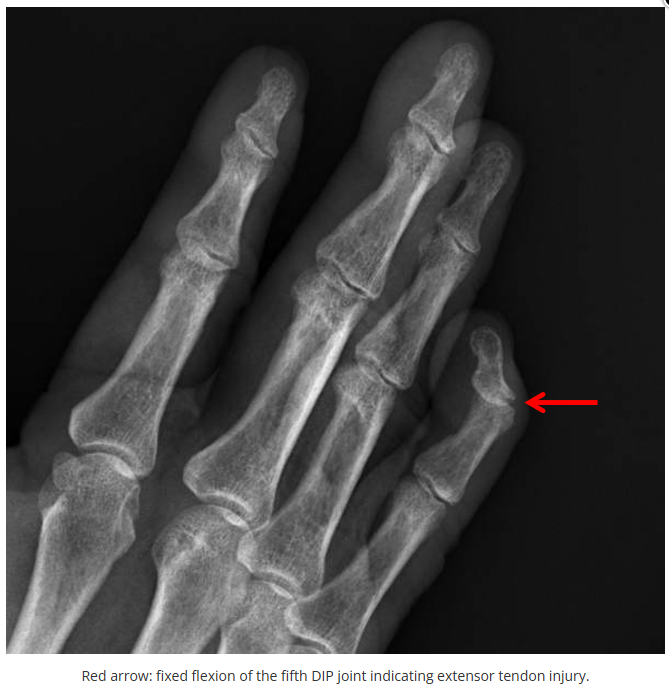

今天是腕部与手的X线片。所有X线片都

带有标注和说明

,可以选择长按图片,

自动翻译相关说明

。